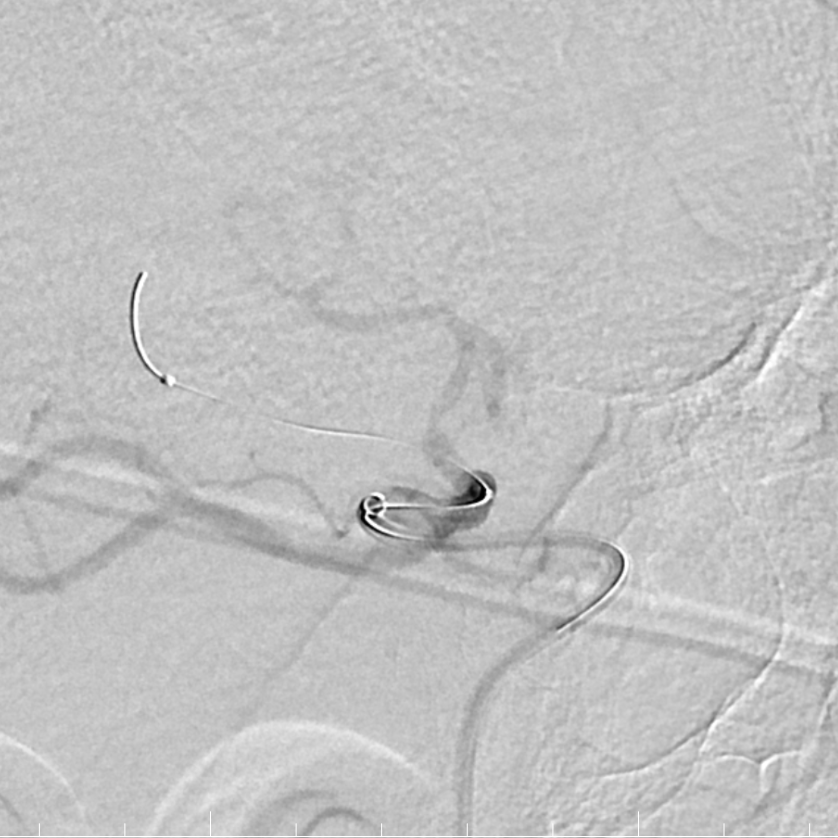

Tarvos微导丝轻松超选,到达M1段。

动脉长鞘怎么置入有励可说|Locaste 088励楷长鞘及Tarvos微导丝在右侧大脑中动脉M2段取栓术中的应用_https://www.jmylbn.com_新闻资讯_第12张

动脉长鞘怎么置入有励可说|Locaste 088励楷长鞘及Tarvos微导丝在右侧大脑中动脉M2段取栓术中的应用_https://www.jmylbn.com_新闻资讯_第13张

Tarvos微导丝携微导管到位。

动脉长鞘怎么置入有励可说|Locaste 088励楷长鞘及Tarvos微导丝在右侧大脑中动脉M2段取栓术中的应用_https://www.jmylbn.com_新闻资讯_第14张

支架释放,采用SWIM技术取栓。